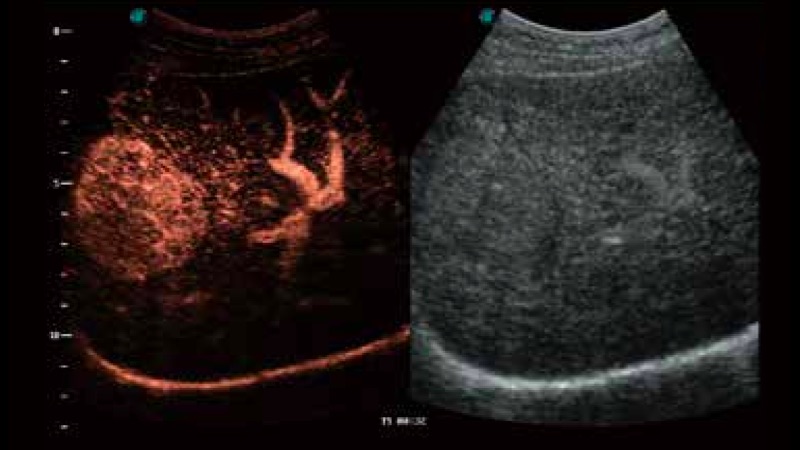

凭借开立医疗先进的成像技术和优异的探头技术提供的清晰的图像表现,您可以更自信地做出临床决策。